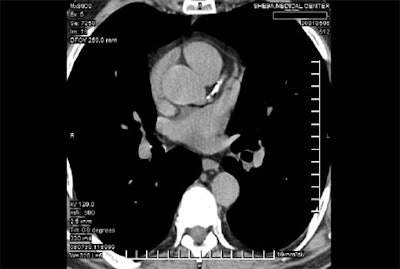

In a study presented at the 2001 RSNA meeting, Dr. Joseph Shemesh from the Sheba Medical Center in Tel-Hashomer, Israel, examined the different characteristics of coronary calcification in patients with acute versus chronic coronary events. The patients were a subgroup of the INSIGHT (International Nifedipine Gastrointestinal Transport System) calcification side arm study, which examined the safety and utility of calcium antagonists in patients with hypertension.

The study examined the extent and characteristics of calcific atherosclerotic lesions in acute versus chronic coronary events. Fifty hypertensive patients (mean age 66.6 years, 78% male) underwent ungated dual-slice spiral CT imaging using a Marconi Mx8000D dual-slice scanner (Philips Medical Systems North America, Bothell, WA).

All of the patients sustained a coronary event during the 3-year follow-up, and all had undergone spiral CT imaging within 12 months prior to the event. The coronary calcium (CC) score was calculated at the proximal 6 cm of the coronary tree.

A total of 883 calcific lesions (defined as 0.5 mm or larger and > 90 HU) were identified in the patients. The researchers calculated the number of lesions, number of vessels with CC, total density of the lesions, and total CC score (TCS) for each patient. The presence of calcium was defined as TCS > 0, Shemesh said.